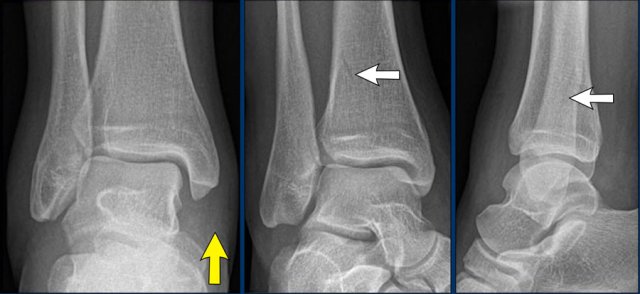

case 4 - distortion

The only thing that we notice is soft tissue swelling especially on the medial side.

Continue with the ankle injury algoritm...

Injury to the medial collateral bands can be seen in Weber B fracture stage 4.

However there are no signs of a WeberB fracture.

The other possibility is that there is a Weber C fracture with a high fibula fracture, that is not visible on the x-rays of the ankle.

The medial band rupture is stage 1 and the injury may stop there or continue to stage 2,3 or even 4.

We need additional x-rays of the entire lower leg to find out which stage we are dealing with.

Continue with the x-rays of the lower leg...

A high fibula fracture is seen (Maisonneuve).

Usually the patient will only feel pain at the level of the ankle since ligament ruptures are very painful and not notice the fibula fracture.